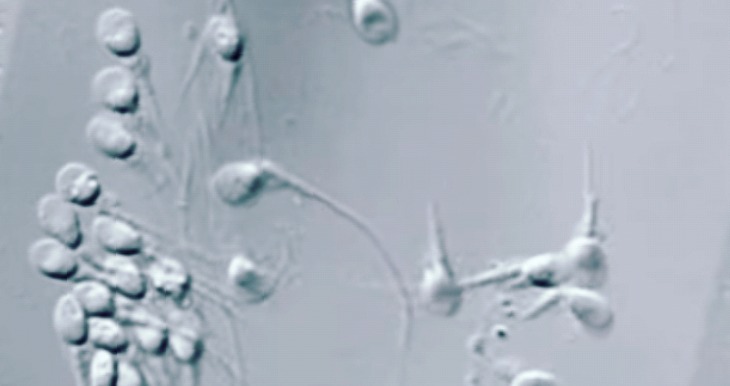

It involves the use of a high magnification DIC (differential interface contrast) microscopy to aid in the precise evaluation and selection of sperm cell prior to injection into the egg.